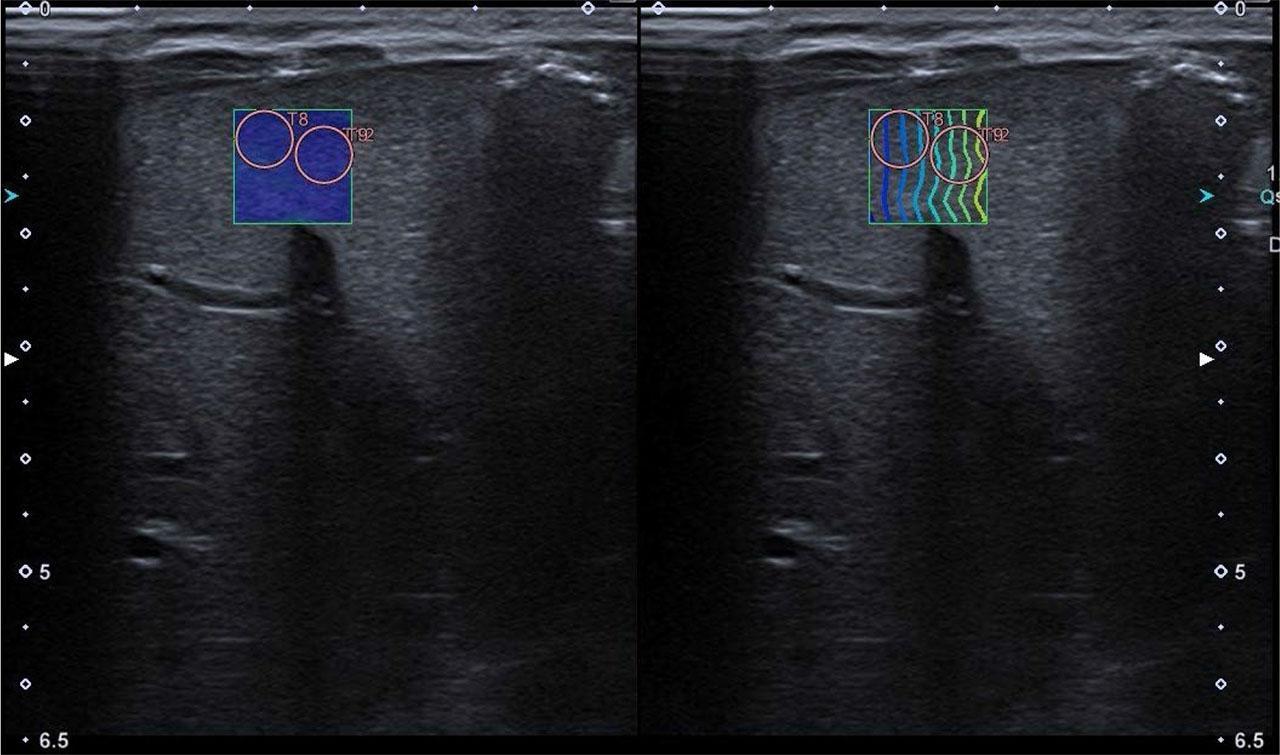

Hepatic, splenic and renal elasticity was measured using the 2D-SWE method during an ultrasound examination (the same device and transducer used for B-mode US), with Canon Aplio i600 system, a14L5 linear transducer (10 MHz), neonatological preset, in spontaneously breathing newborns. A minimum food intake interval of 60 minutes was required. The liver and spleen were assessed with the newborn in the supine position. The right hepatic lobe was assessed under the right costal arch or in the right intercostal space, the left hepatic lobe was assessed in the midline, under the costal arch, achieving optimal transducer placement. The spleen was examined in the left intercostal space or under the left costal arch, achieving optimal transducer placement. The kidneys were assessed in the prone position, from the dorsal side, in the middle part of the kidney, in the view transverse to the long axis. The transducer was placed perpendicularly to the surface of the examined organs, avoiding additional pressure with the transducer. Before taking measurements, a color-coded uniform area of the measurement map (elastogram) was determined using the wave propagation map (option available in the device). The measurements were done below the organ capsule, with the ROI placed within the elastogram so that it was filled with a uniform color, and with wave lines arranged in parallel, equally spaced on the propagation map. The above steps were repeated to obtain a series of 5 measurements (ROI). The ROI size was 5 mm for the right and left lobes of the liver, spleen and kidneys. Examples of 2D-SWE examinations of the right and left lobes of the liver, spleen and kidney are illustrated in Fig. 1, Fig. 2, Fig. 3, Fig. 4. In the kidney examination, the ROI included the renal parenchyma (cortex and pyramid) in such a way that the position of the pyramid (long axis) was parallel to the US beam, excluding the lumens of the calyces and the renal pelvis. The results for each organ were obtained based on the calculation performed by the application installed by the manufacturer in the US device, based on a series of 5 measurements.

An exemplary SWE measurement of the right liver lobe with a color-coded map and a wave propagation map, two ROIs are marked

An exemplary SWE measurement of the left liver lobe with a color-coded map and a wave propagation map, two ROIs are marked